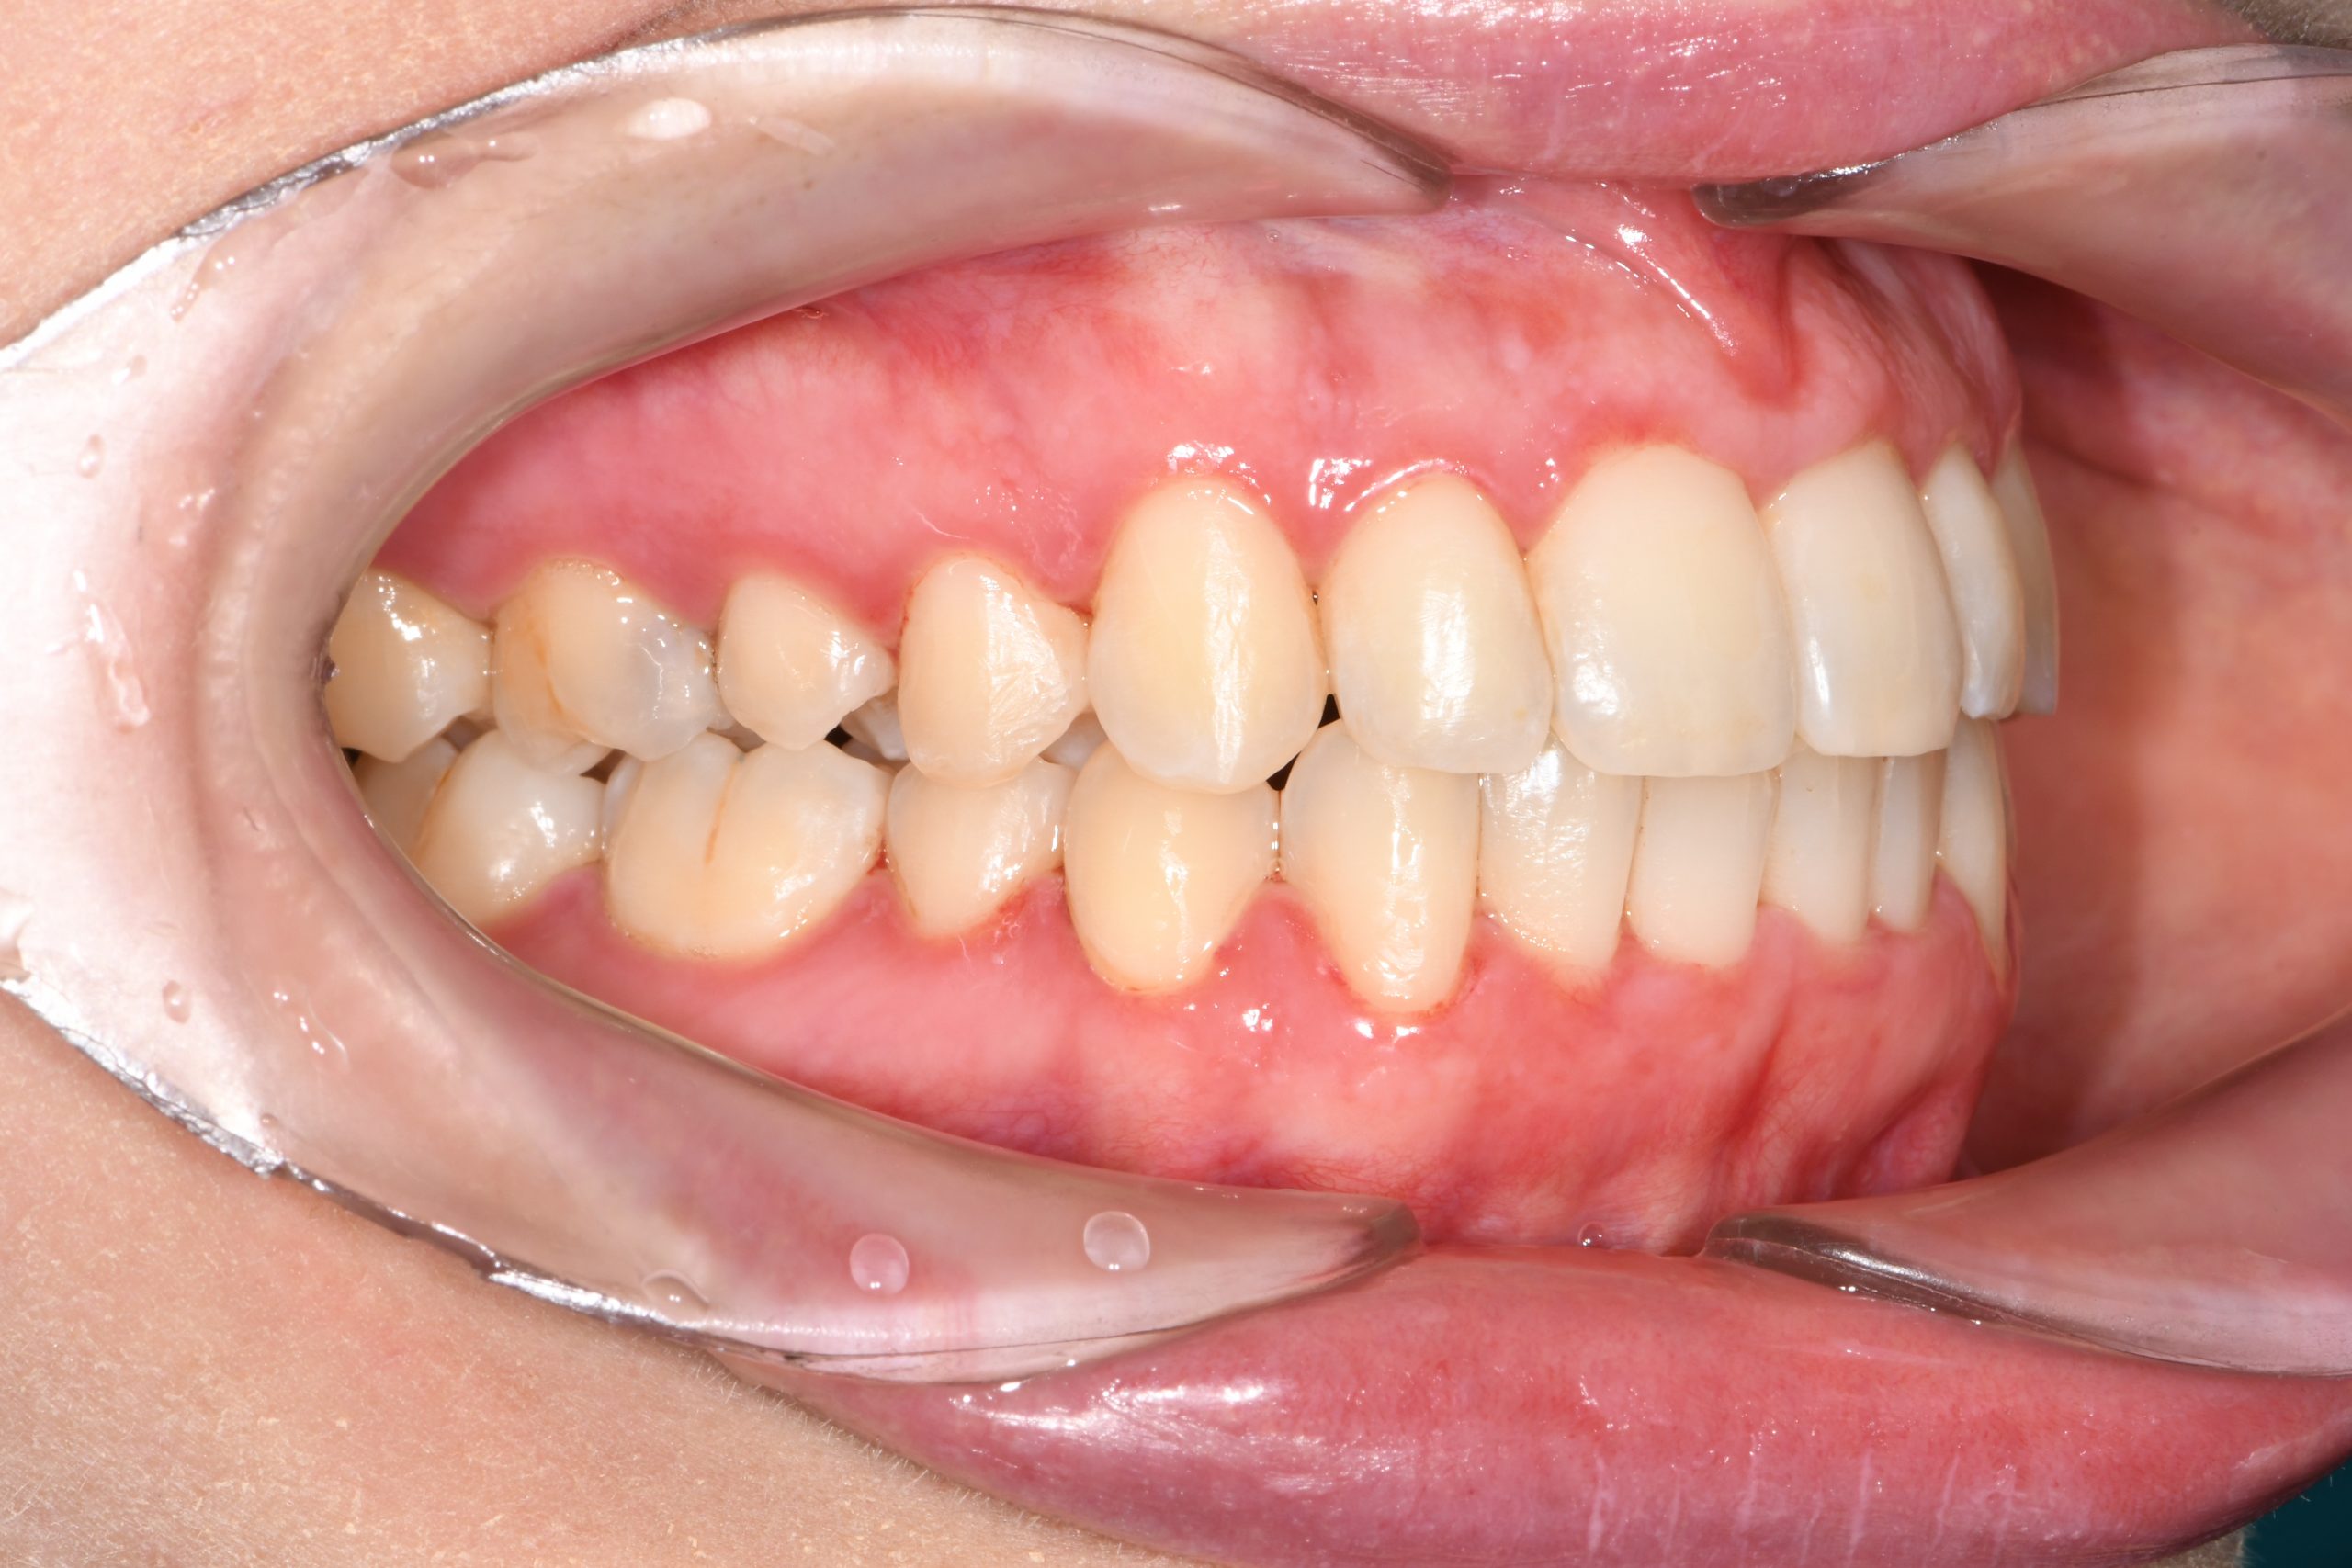

Az elmúlt évekből rengeteg szakmai referenciát tudnánk bemutatni, amelyek különböző fogszabályozási problémákat oldottak meg. Válogatva a több száz esetből, ezen az oldalon olyan képeket, információkat igyekeztünk bemutatni, amelyeknek a segítségével a jövőbeni pácienseinknek azt tudjuk üzenni: A Te fogsorod is lehet gyönyörű!